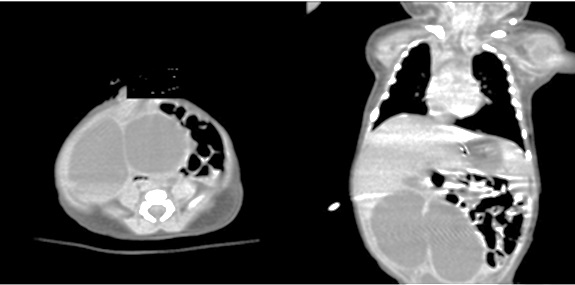

A 2-day-old (3.2kg) full-term male neonate, a prenatally diagnosed case of a large intra abdominal cystic mass and born by a simple vaginal delivery, was ventilated immediately after birth because of respiratory distress. The routine initial laboratory data showed anemia (Hb 11.4 g/dl with Hct 33.6%), thrombocytopenia (120,000/ml), slightly elevated liver enzymes (AST 130 U/l, ALT 112 U/l), and hyperbilirubinemia (2.6 mg/dl). CT scan of the abdomen revealed an ill-defined large-sized (10.5× 8.6× 6.3cm) multilocular cystic lesion with thick enhancing walls, occupying the right side of the abdomen and diagnosed radiologically as a huge mass related to the liver with all bowel loops were pushed to the other side (Fig. 1).

The US picture of IHH can be highly variable. Solitary lesions can have a heterogeneous echogenicity, and the Doppler spectral analysis can show a variety of flow patterns.On CT with intravenous contrast, IHH will either enhancediffusely or show rim enhancement that is followed by gradual filling of the center of the lesion. In one seriesthe CT enhancement pattern was correlated to the size of the lesions. Lesions less than 1 cm enhanced homogeneously inthe arterial phase. Lesions greater than 2 cm demonstrated peripheral rim enhancement.Unfortunately, the classic enhancement patterns are not always present in IHH, which can make the radiologic diagnosis more difficult.[7] In the present case, the CT scan couldn’t confirm the preoperative diagnosis of hepatic hemangioma may be due to its huge size and presence of blood clotting in vascular spaces. MRI is emerging as the single most useful modality to show both the location of the hemangioma, its flow pattern,and the structure.[8] MRI is considered an excellent diagnostic modality but unfortunately was not available in the index case.

Figure 1

CT scan of the abdomen revealed multilocular huge cystic mass related to the liver with thick enhancing wall.